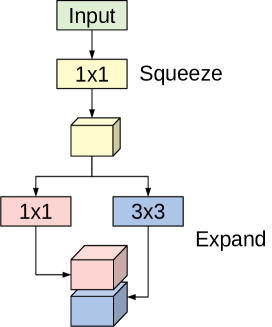

The SqueezeNet architecture is a deep CNN proposed for computer vision tasks with the main concerns on efficiency (having fewer parameters and smaller model size) [39]. The basic building block for the SqueezeNet architecture is the fire module depicted in Figure 1. The module incorporates the squeeze phase and the expand phase. The squeeze phase applies a set of filters followed by a ReLU activation. The number of learned squeeze filters is always smaller than the size of the input volume. Consequently, the squeeze phase can be considered as a dimensionality reduction process, and at the same time it captures the pixel correlations across the input channels. The output of the squeeze phase is fed into the expand phase, in which a combination of and convolutions are learned. The larger filters are used to capture the spatial correlation amongst pixels. The outputs of the expand phase are concatenated across the channel dimension and then evaluated by a ReLU activation.

The original paper proposed using , ; and , filters in the expand phase, where is larger than number of filters used in the squeeze phase. The entire SqueezeNet architecture is constructed by stacking conventional convolution layers, max-pooling, fire modules, and ends with an average pooling layer. The model has no fully connected layers. For more details about the number of fire modules for each stage, their order, and number of squeeze and expand filters for the different stages, see [39].